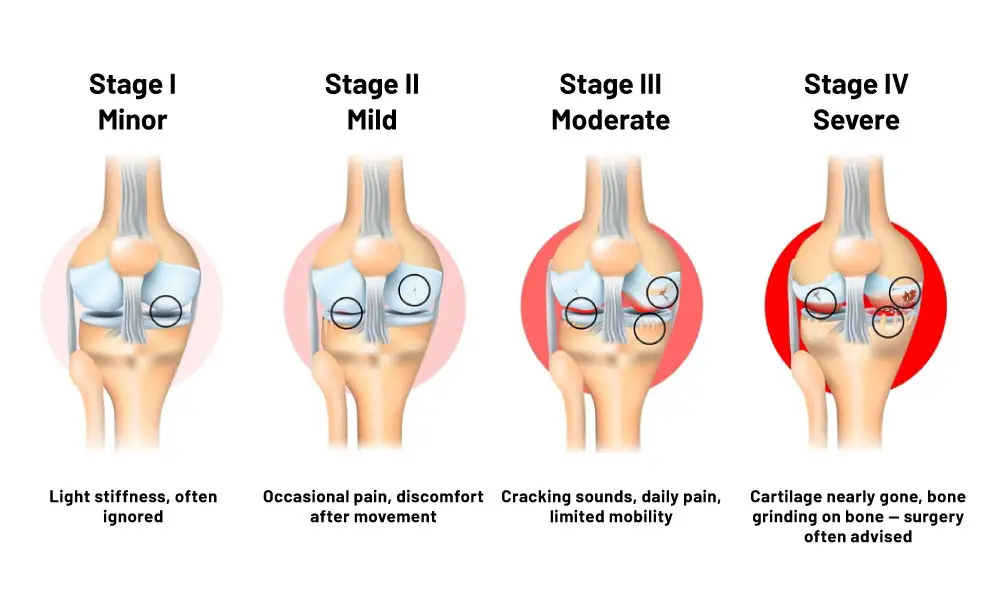

Are You At Stage 3 Without Knowing It? The 4 Steps of Knee Decline

Studies show that over 30% of untreated patients report a loss in independence.

Stiffness in the morning. (Often ignored until it’s too late).

Pain when climbing stairs. (You start relying on painkillers).

Relying on a cane or walker. Bone grinding on bone. Daily life becomes a struggle for independence.

Permanent disability or high-risk surgery is the only option left.

This is your final window to reverse the damage naturally before Stage 4 becomes permanent.

But here’s the truth: Pain is only the symptom. The real problem is joint degradation, specifically osteoarthritis.

➡️ It starts with the loss of cartilage — the soft cushion and the reduction of joint fluid, which keeps everything moving smoothly.

➡️ Then our two joint bones begin to rub directly against each other. Which only leads to inflammation, soreness, stiffnes,s and eventually pain.